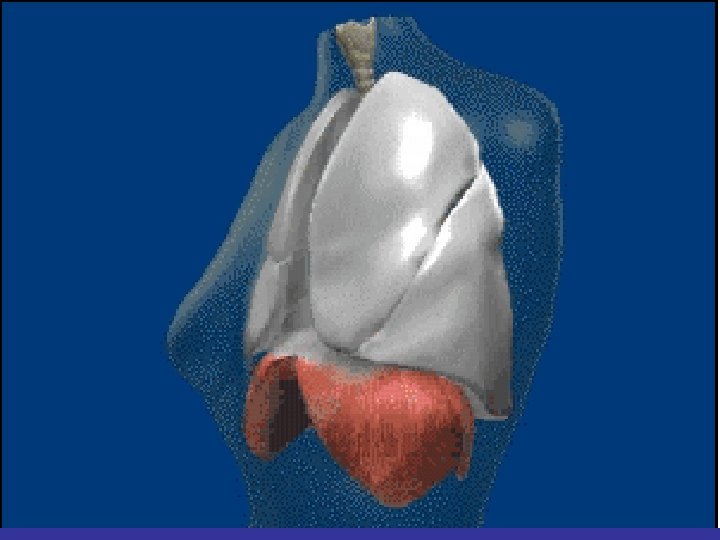

lateral view ? ! can detect otherwise hidden masses

The lateral chest film our best friend • Find abnormalities on the frontal film

The lateral chest film our best friend • Find abnormalities on the frontal film • Confirm abnormalities suspected from frontal film • Don’t be afraid to look at it